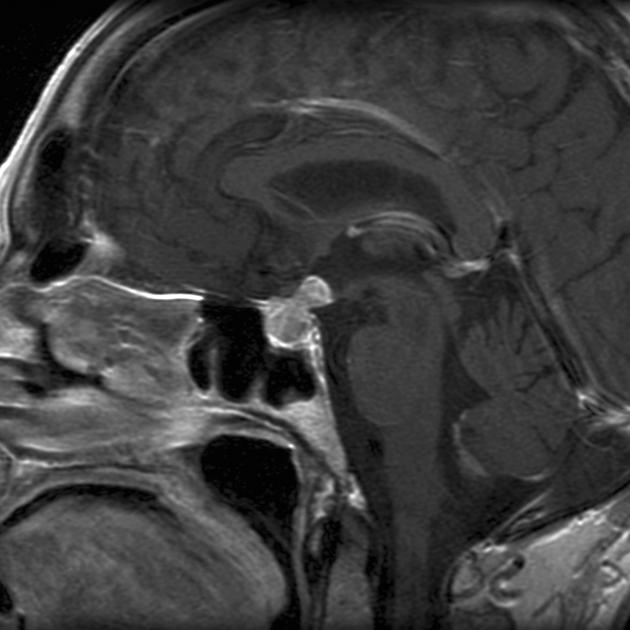

Di căn tuyến yên (Pituitary Metastases)

• Di căn tuyến yên (Pituitary Metastases)